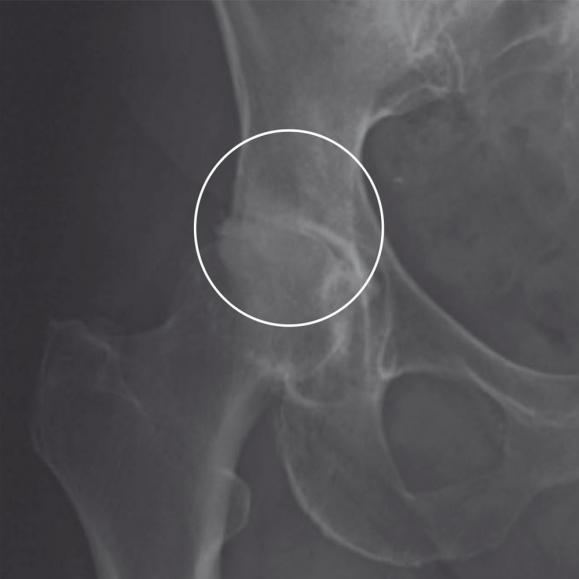

Entfernung des Hüftkopfes

Der erkrankte Hüftkopf wird vom Oberschenkelhals abgetrennt und entnommen.

Versorgung der Hüftpfanne

Nun wird die am Beckenknochen befindliche Hüftpfanne für die Implantation vorbereitet. Mit einer speziellen Fräse formt der Herr Petersen das Implantatbett. Dort wird dann die künstliche Hüftpfanne befestigt. Das geschieht meist mit Pressdruck, selten mit Zement oder verschraubt.

Versorgung des Oberschenkels

Der Markraum des Oberschenkelknochens wird mit Spezialraspeln aufgeraut und für die Aufnahme des Hüftschafts vorbereitet. Dieser wird in den Markraum des Oberschenkelknochens eingesetzt. Darauf wiederum wird dann der Hüftkopf aufgesetzt. Hier besteht die Wahl zwischen einer Einzementierung des Schaftes mit Knochenzement oder einem Einbringen, bei dem der Knochen langsam mit dem Schaft zusammenwächst. Je nach körperlichen Voraussetzungen kann für Sie die eine oder andere Variante angeraten sein. Beraten Sie sich mit Ihrem Facharzt Herrn Carsten Petersen, um die für Sie beste Befestigungsart zu ermitteln. Ist der Schaft in den Oberschenkelknochen eingebracht, wird der Hüftkopf auf seinem Hals befestigt.